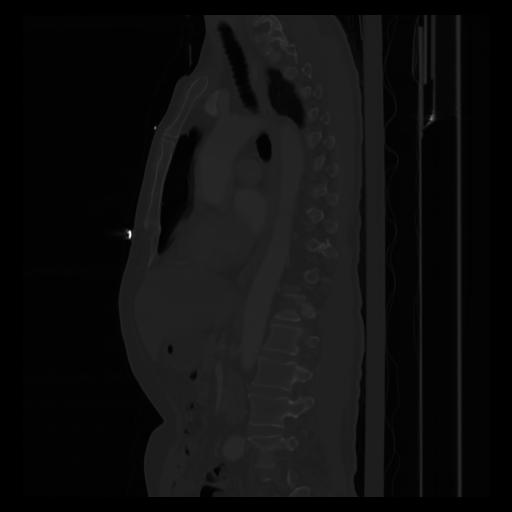

30 CUERPO,CE,Sagittal,3.000,CUERPO,Sagittal,